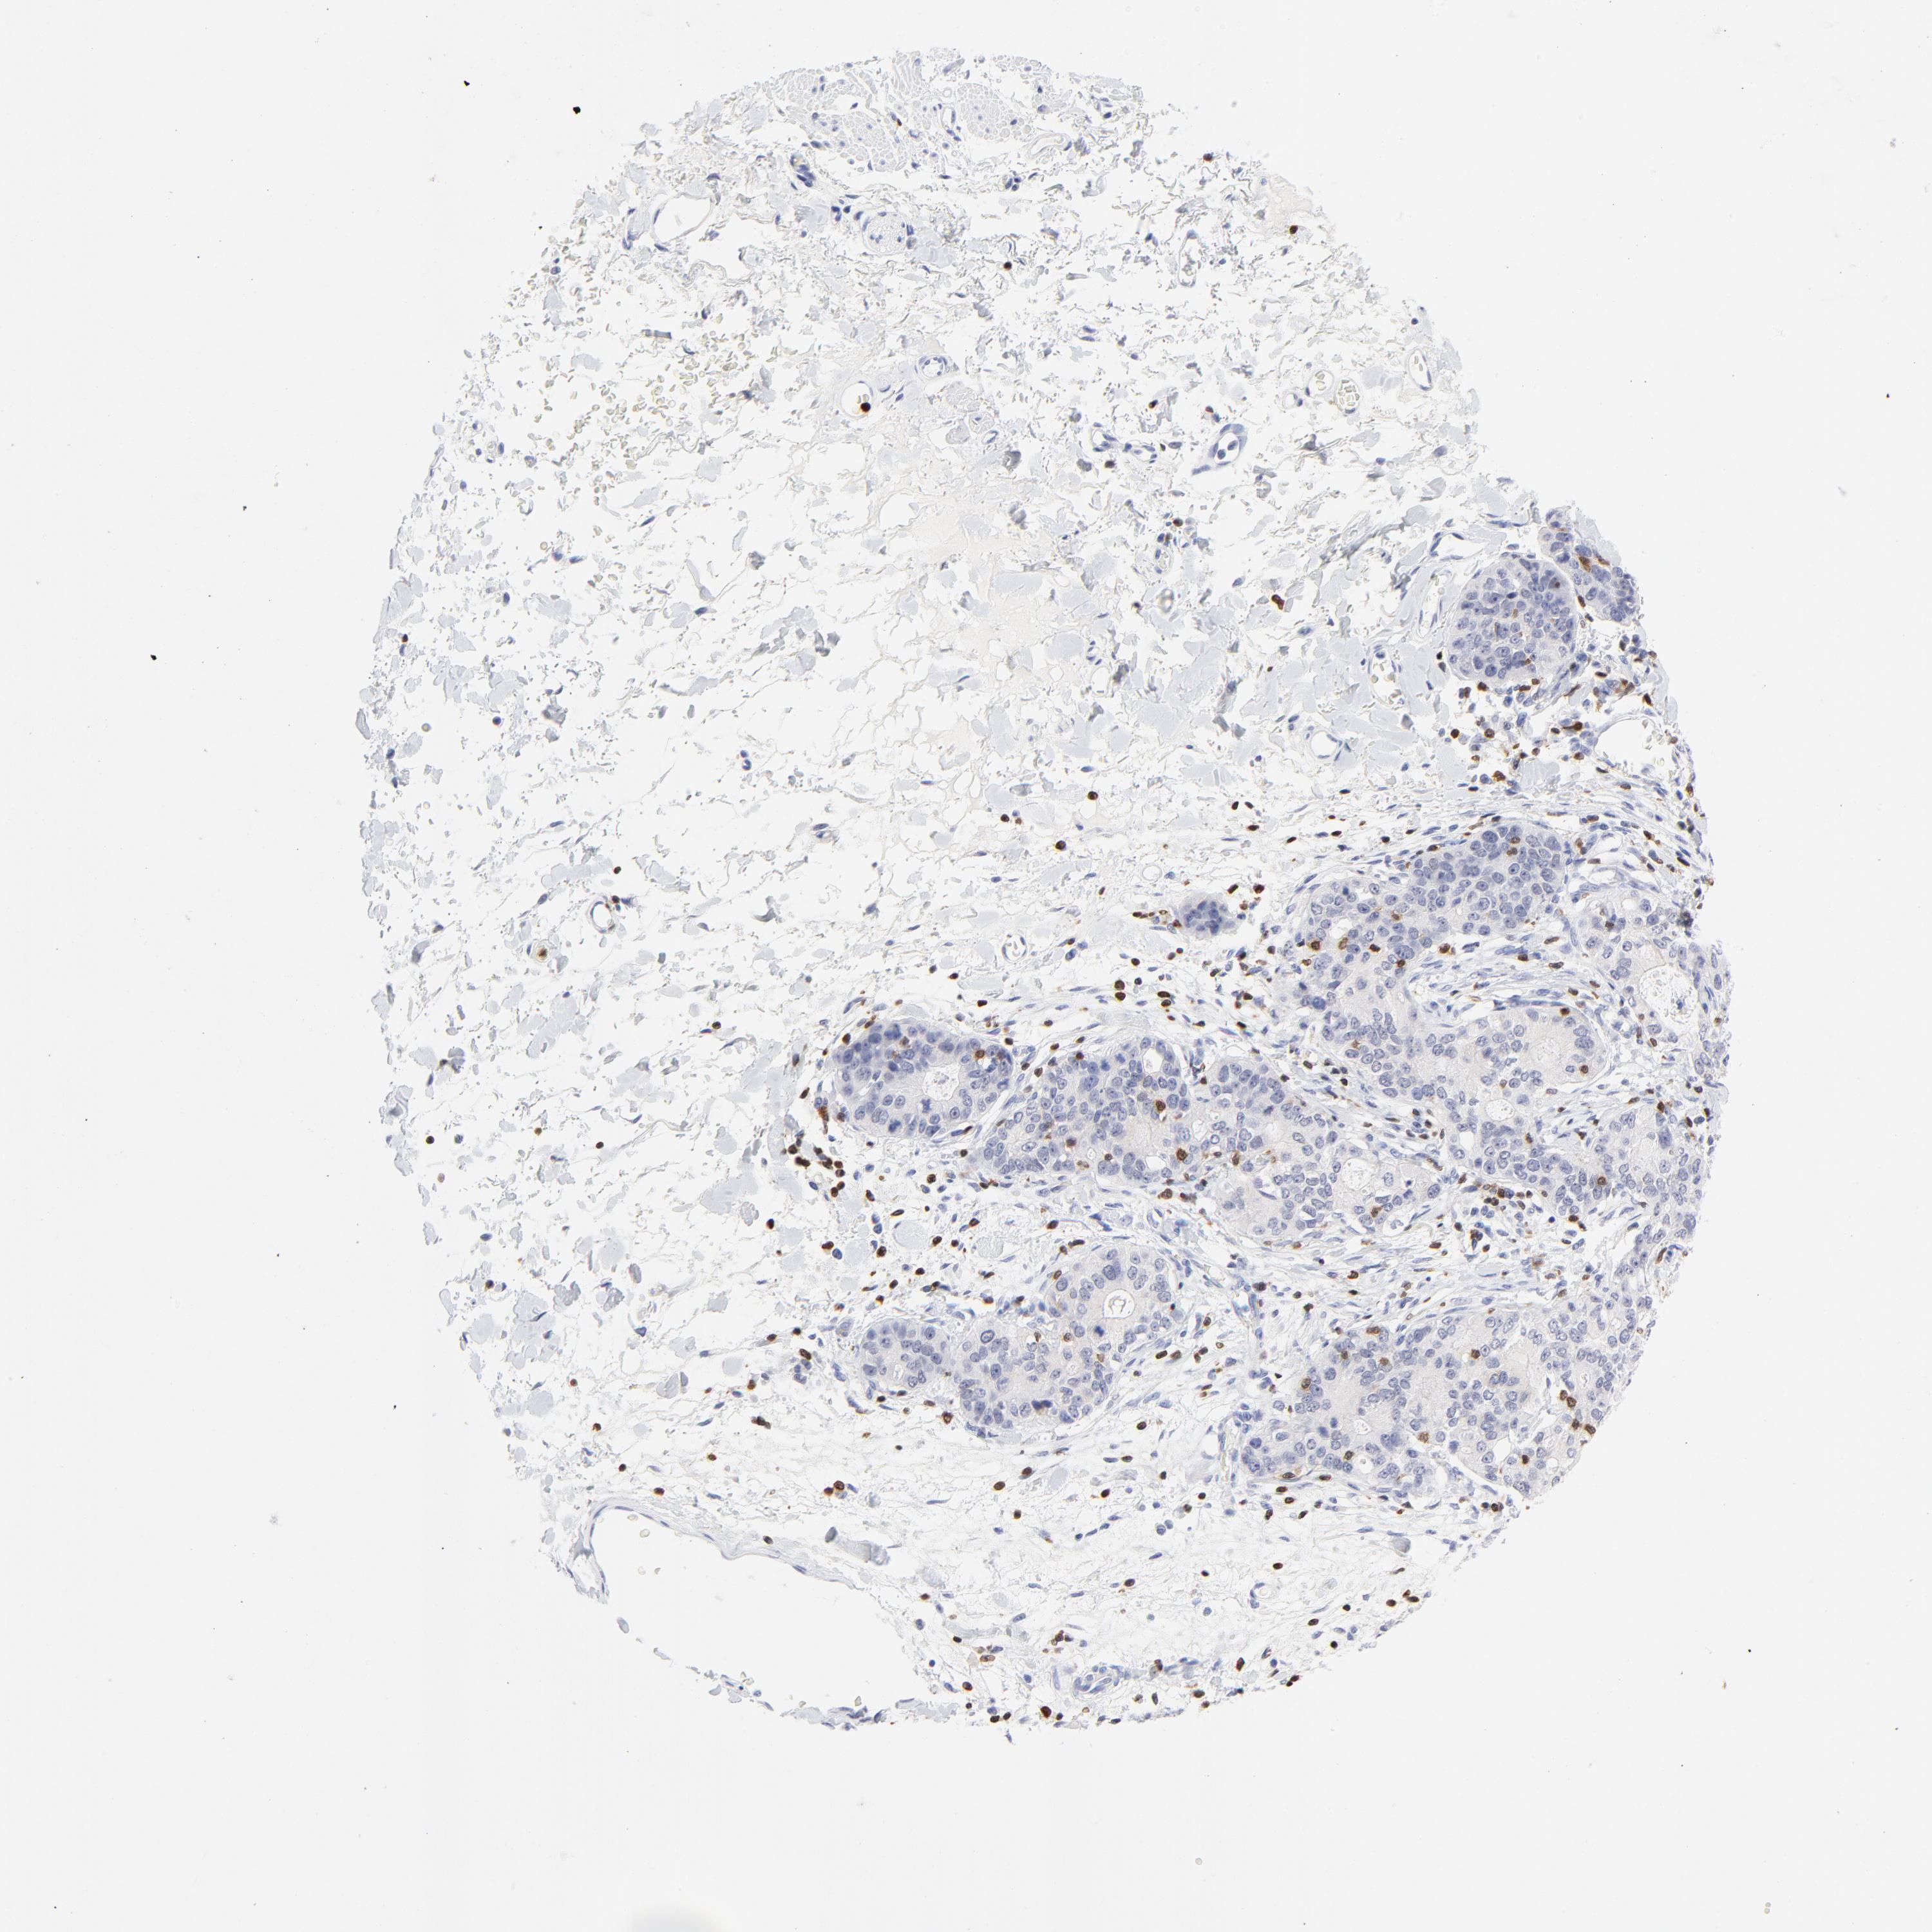

STOMACH CANCER - Protein expressioni

A mouse-over function shows sample information and annotation data. Click on an image to view it in a full screen mode. Samples can be filtered based on level of antibody staining by selecting one or several of the following categories: high, medium, low and not detected. The assay and annotation is described here.

Note that samples used for immunohistochemistry by the Human Protein Atlas do not correspond to samples in the TCGA dataset.

Antibody stainingi

Antibody staining in the annotated cell types in the current human tissue is reported as not detected, low, medium, or high, based on conventional immunohistochemistry profiling in selected tissues. This score is based on the combination of the staining intensity and fraction of stained cells.

Each image is clickable and will lead to virtual microscopy that enables deeper exploration of all samples and also displays staining intensity scores, fraction scores and subcellular localization as well as patient and tissue information for each sample.

Antibody HPA003134

Antibody CAB002625

Staining

High

Medium

Low

Not detected

Intensity

Strong

Moderate

Weak

Negative

Quantity

>75%

75%-25%

<25%

None

Location

Nuclear

Cytoplasmic/membranous

Cytoplasmic/membranous,nuclear

Adenocarcinoma, NOS